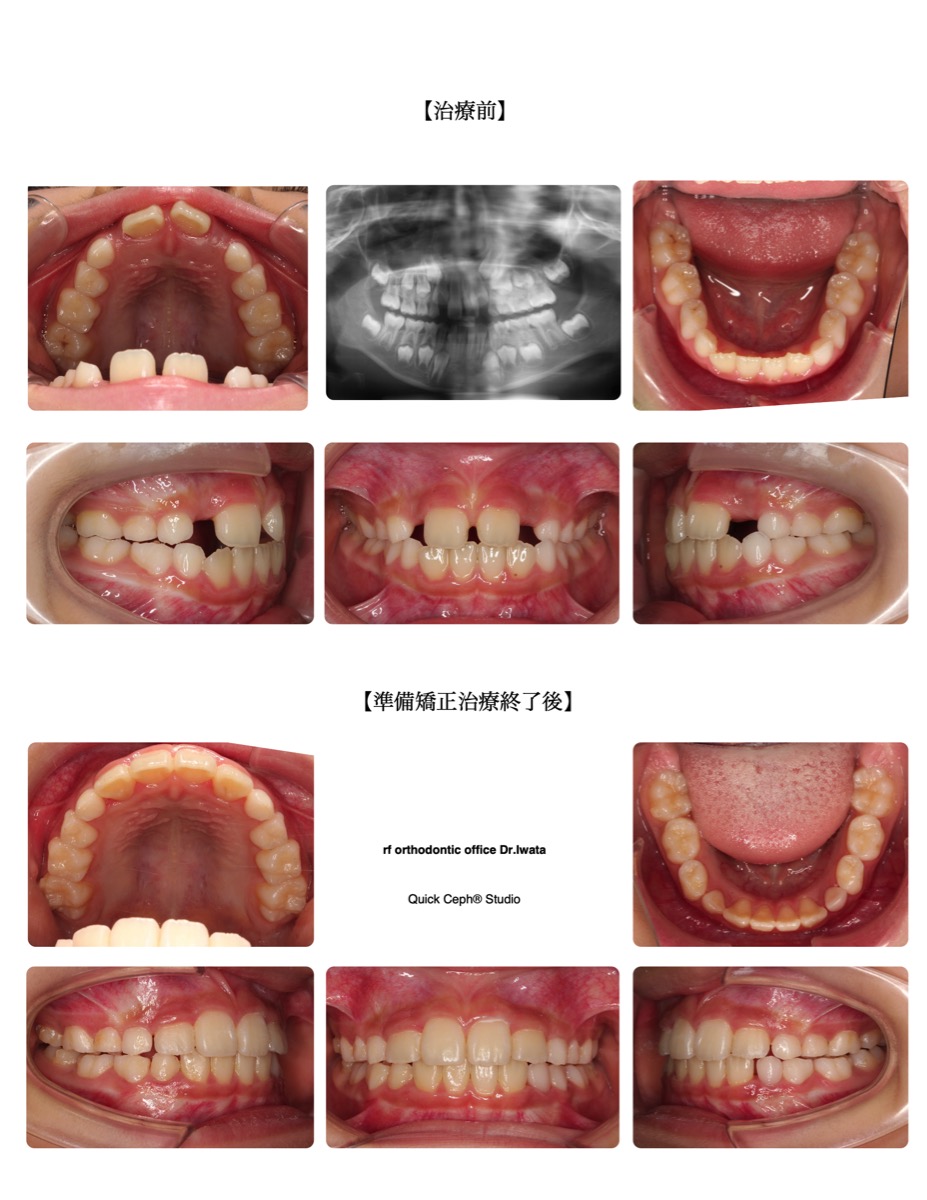

【主訴】上の前歯がすきっ歯で隣の歯がなかなか出てこない。下の前歯もちょっとガタガタになっている。

【主な症状】空隙歯列(正中離開) 叢生

| 治療期間・回数 | 13ヶ月・12回 |

| 年齢 | 7歳 |